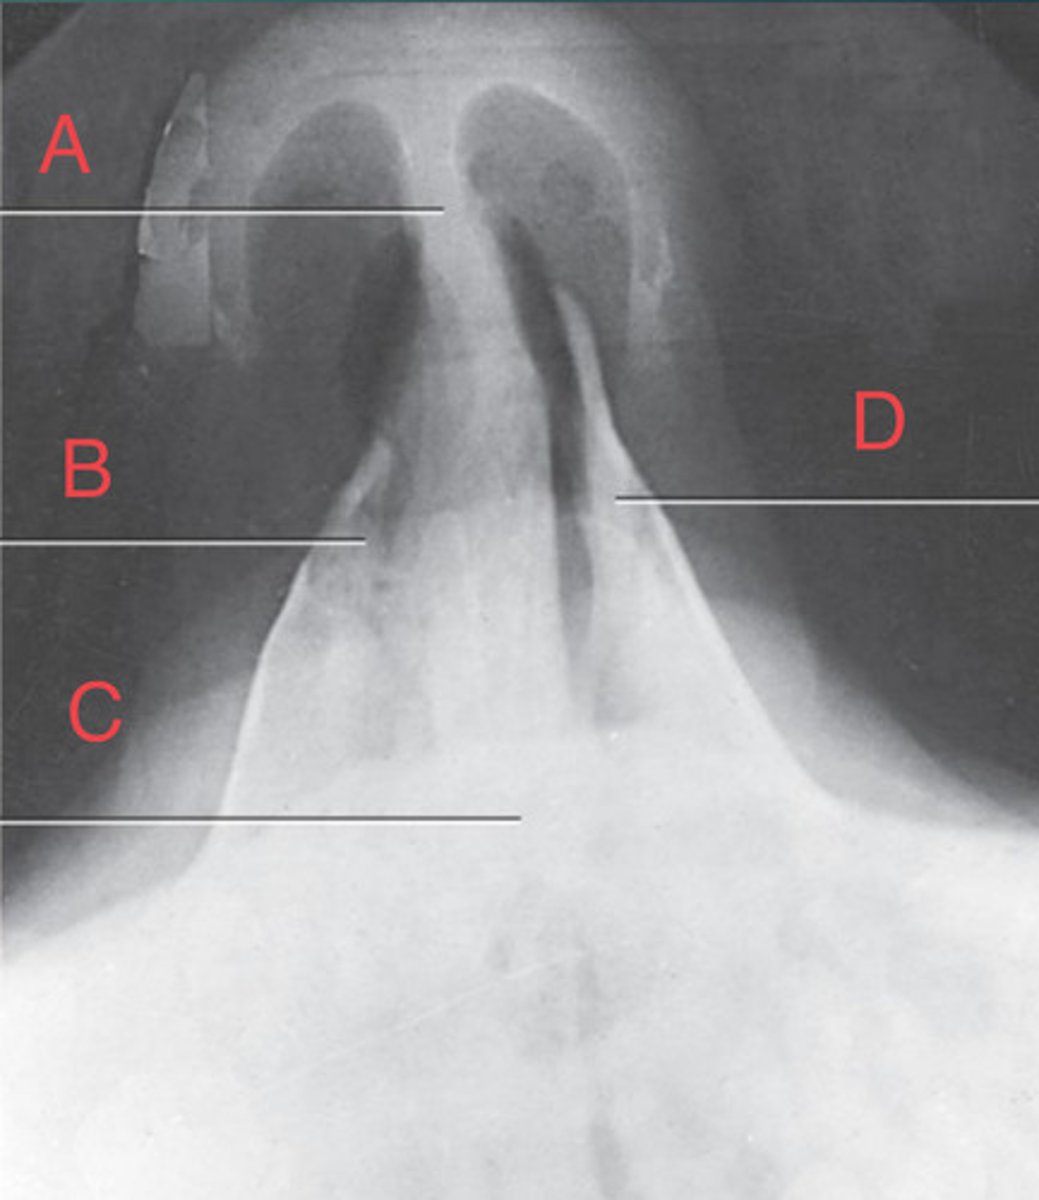

PA Caldwell Sinuses

What position?

frontal sinus of the frontal bone

A.

R. ethmoid sinus of the ethmoid bone

B.

crista galli of ethmoid bone

C.

L superior orbital fissure of the sphenoid

D.